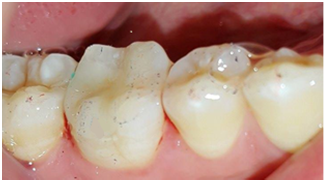

The vitality test revealed a positive response of the 46. The radiological examination showed a large-scale amalgam restoration at a distance from the pulp (Figure 2). After clinical examination, the appropriate treatment option was a ceramic onlay restoring the 46 using the IPS e.max CAD system.

Figure 2 Periapical radio on the 46: a large-scale amalgam.